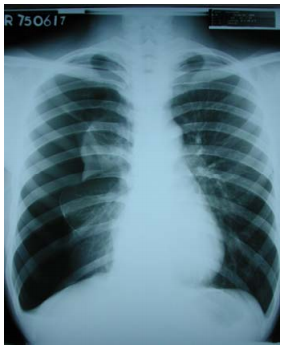

35 一位 21 歲男性患者,因胸痛及呼吸困難前來就診,胸部 X 光片如圖所示,下列何種處置最為適當?

(A)即時給予抗生素治療 (B)給予支氣管擴張劑吸入治療 (C)插胸管引流 (D)給予氧氣治療,並觀察病情